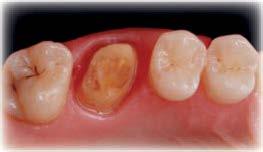

Elevación de seno transcrestal con implantes cortos versus elevación de seno convencional con ventana lateral

Estudio retrospectivo comparativo a boca partida

La rehabilitación del maxilar superior posterior mediante implantes dentales se ha visto condicionada clásicamente por la neumatización excesiva del seno maxilar al perderse los dientes relacionados con el mismo (dientes antrales) (1, 2). En estos casos, se pierde gran parte de la altura del reborde óseo residual generándose atrofias verticales, que pueden limitar, de forma importante, la inserción de implantes de manera directa (3-5).

Esta ocupación del seno de la cresta residual adyacente es diferente en función del diente a extraer, la pérdida ósea asociada a ese diente y la presencia, o no, de comunicación de la potencial infección odontógena con el seno. Aun así, es frecuente que la mayor pérdida en altura derivada del proceso de neumatización del

seno post-extracción sea para el segundo molar o cuando se realiza la extracción del primer y segundo molar simultáneamente (6). Cuando los dientes se han perdido y el seno ha ocupado gran parte del volumen óseo residual de la zona del maxilar superior en su zona posterior, clásicamente, se realizaba una técnica de elevación de seno por abordaje lateral para, mediante un injerto óseo compuesto por diferentes materiales (hueso autólogo, biomaterial o mezcla de ambos generalmente), volver a recuperar la altura de cresta ausente y poder insertar los implantes dentales posteriormente o en el mismo procedimiento, siempre que existiese un volumen óseo residual que permitiese que los implantes quedaran estables (7-9).

como los implantes cortos, extracortos y actualmente también los ultracortos, que hacen que sea posible insertar los implantes de forma directa en volúmenes de hueso muy reducidos (alturas residuales en torno a los 5 mm), donde clásicamente se hubiese llevado a cabo una elevación de seno (10-13).

Estos implantes permiten, por lo tanto, la inserción sin técnicas accesorias en una única cirugía y con un procedimiento menos traumático para el paciente, a la vez que más predecible, al englobarse un menor número de factores quirúrgicos que pueden generar efecto negativo en el proceso (cicatrización, integración del injerto, dehiscencia y exposición del injerto, perforación de la membrana de Schneider, obstrucción del seno, etc.) (12, 13).

Aún así, existen hoy en día situaciones en las que la inserción de un implante corto o extra-corto no es posible de forma directa, cuando existe un volumen óseo residual por debajo de los 5 mm, existiendo en estos casos una nueva alternativa terapéutica a la elevación de seno convencional que es la elevación de seno transcrestal (14-15).

En esta técnica se accede a través de la cresta mediante la confección de un neoalveolo generado por fresado al seno maxilar despegándose la membrana desde este neoalveolo e insertándose el implante corto o extra-corto con o sin injerto asociado (en función del volumen en altura que se pretende ganar) (14-15).

Ya que ambas técnicas quirúrgicas siguen hoy en día en pleno auge, aunque las indicaciones para cada una de ellas han evolucionado en el tiempo, quedando la elevación convencional únicamente indicada hoy en día en aquellos casos de 1-2 mm de volumen óseo residual (donde es muy complejo estabilizar un implante corto por elevación transcrestal), creemos útil poder comparar la evolución de ambos procedimientos en el tiempo, a ser posible en un mismo paciente, donde el resto de variables que puedan afectar al seguimiento sean iguales, y, por lo tanto, la comparación sea más útil. Por ello, hemos realizado un análisis retrospectivo de pacientes en los que se han realizado los dos procedimientos, uno en cada cuadrante superior y ver la evolución en el tiempo de los implantes insertados en cada caso. Con esta idea en mente, hemos llevado a cabo un estudio retrospectivo que evaluase estos factores, y que se detallan a continuación.

MATERIAL Y MÉTODO

Fueron reclutados de forma retrospectiva pacientes en los que se hubiesen realizado ambas

técnicas de abordaje de seno maxilar: elevación convencional o la inserción de implantes cortos y extra-cortos mediante elevación transcrestal, desde enero de 2010 en adelante. Todos los pacientes fueron estudiados antes de la inserción de los implantes mediante modelos diagnósticos, exploración intraoral y realización de un TAC dental (Conebeam) analizado posteriormente mediante un software específico (BTI-Scan II).